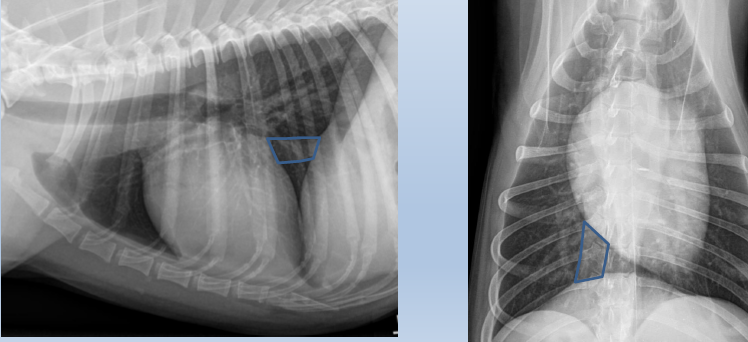

Cardiac silhouette

Caudal mediastinal reflection

Caudal mediastinum

Caudal vena cava

Cranial mediastinum

Cranioventral mediastinal reflection

Descending aorta

Esophagus

2 to 3

Feline

Left atrium

Left auricle

Left Ventricle

Mass on right side

Arteries up and away

Veins ventral and central